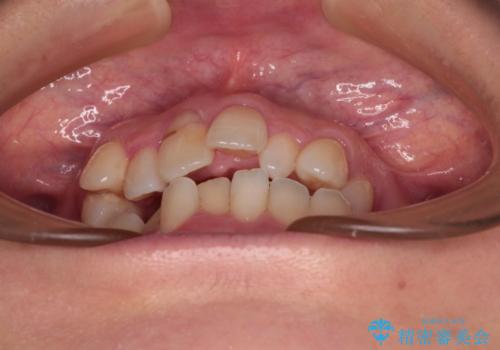

- 前歯のデコボコと咬み合わせの悪さを気にして来院された患者様です。

下顎骨が左側にズレて成長してしまったため、左側の咬み合わせが上下反対になっている状態でした。

骨格的なズレは歯列矯正のみでは改善できず、骨切除が必要となります。

そこまでの処置は望んでいらっしゃらなかったため、歯列矯正でのカムフラージュにより咬み合わせを改善することとしました。